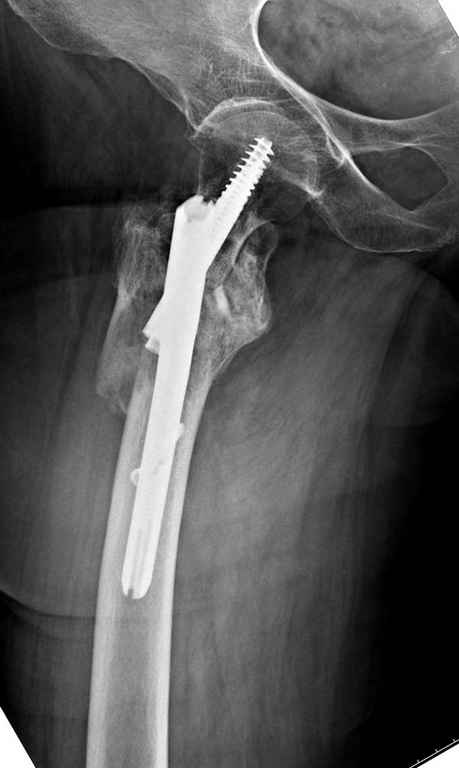

Re: оскольчатый чрезвертельный перелом

А так для лечения оскольчатых переломов подходят все методы, включая интра- и экстрамедуллярные в зависимости от опыта и наличия импланта.

Здесь пара похожих случаев.